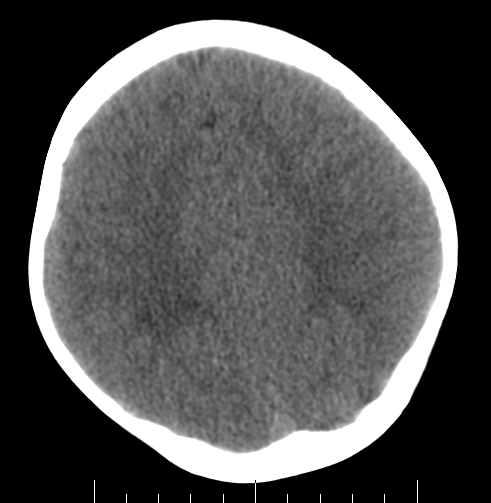

女,3岁,头部外伤一小时。半卵圆中心低密度是什么意思,病灶?侧脑室?请指教。

正常表现

脑白质

幼儿正常脑白质表现,长期观察,必要时mr

从层面看不是侧脑室,考虑低密度变,建议mri。

不是侧脑室,考虑正常脑白质。为慎重,建议mr!